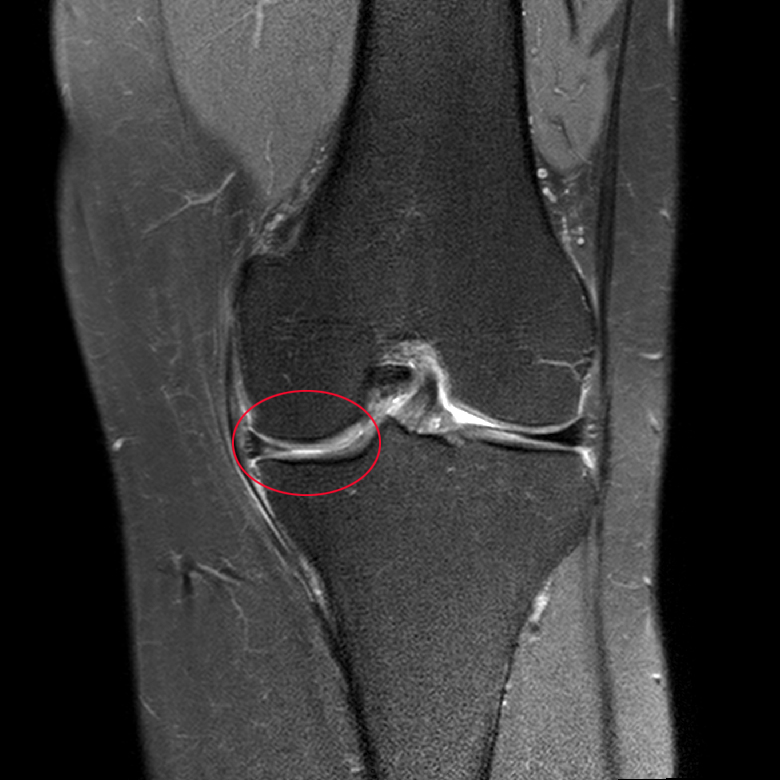

슬관절이라고 부르는 무릎 관절은 크게 대퇴골, 견골, 슬개골 등 세 개의 뼈로 구성되어, 움직이고 체중 부하를 막는 역할을 한다. 이 관절들은 많이 쓰다보면 닳을 수밖에 없다. 따라서 관절의 움직임을 부드럽고 효율적으로 하기 위해서 뼈끝 관절면에 관절 연골이 덮여있다. 이 관절 연골 사이에서 쿠션 역할을 하는 구조물이 ‘반월연골판’으로, 안쪽과 바깥쪽에 각각 C자 모양으로 만들어져 있다.

반월연골판의 가장 큰 역할은 무릎에 부하되는 하중을 받쳐주고, 무릎 관절을 안정적으로 잡아주어 관절을 보호할 뿐 아니라 자연스럽게 움직일 수 있도록 윤활 역할을 한다. 흔히 연골이 파열됐다고 할 때의 연골은 이 ‘반월연골판’을 의미하는 경우가 많다.